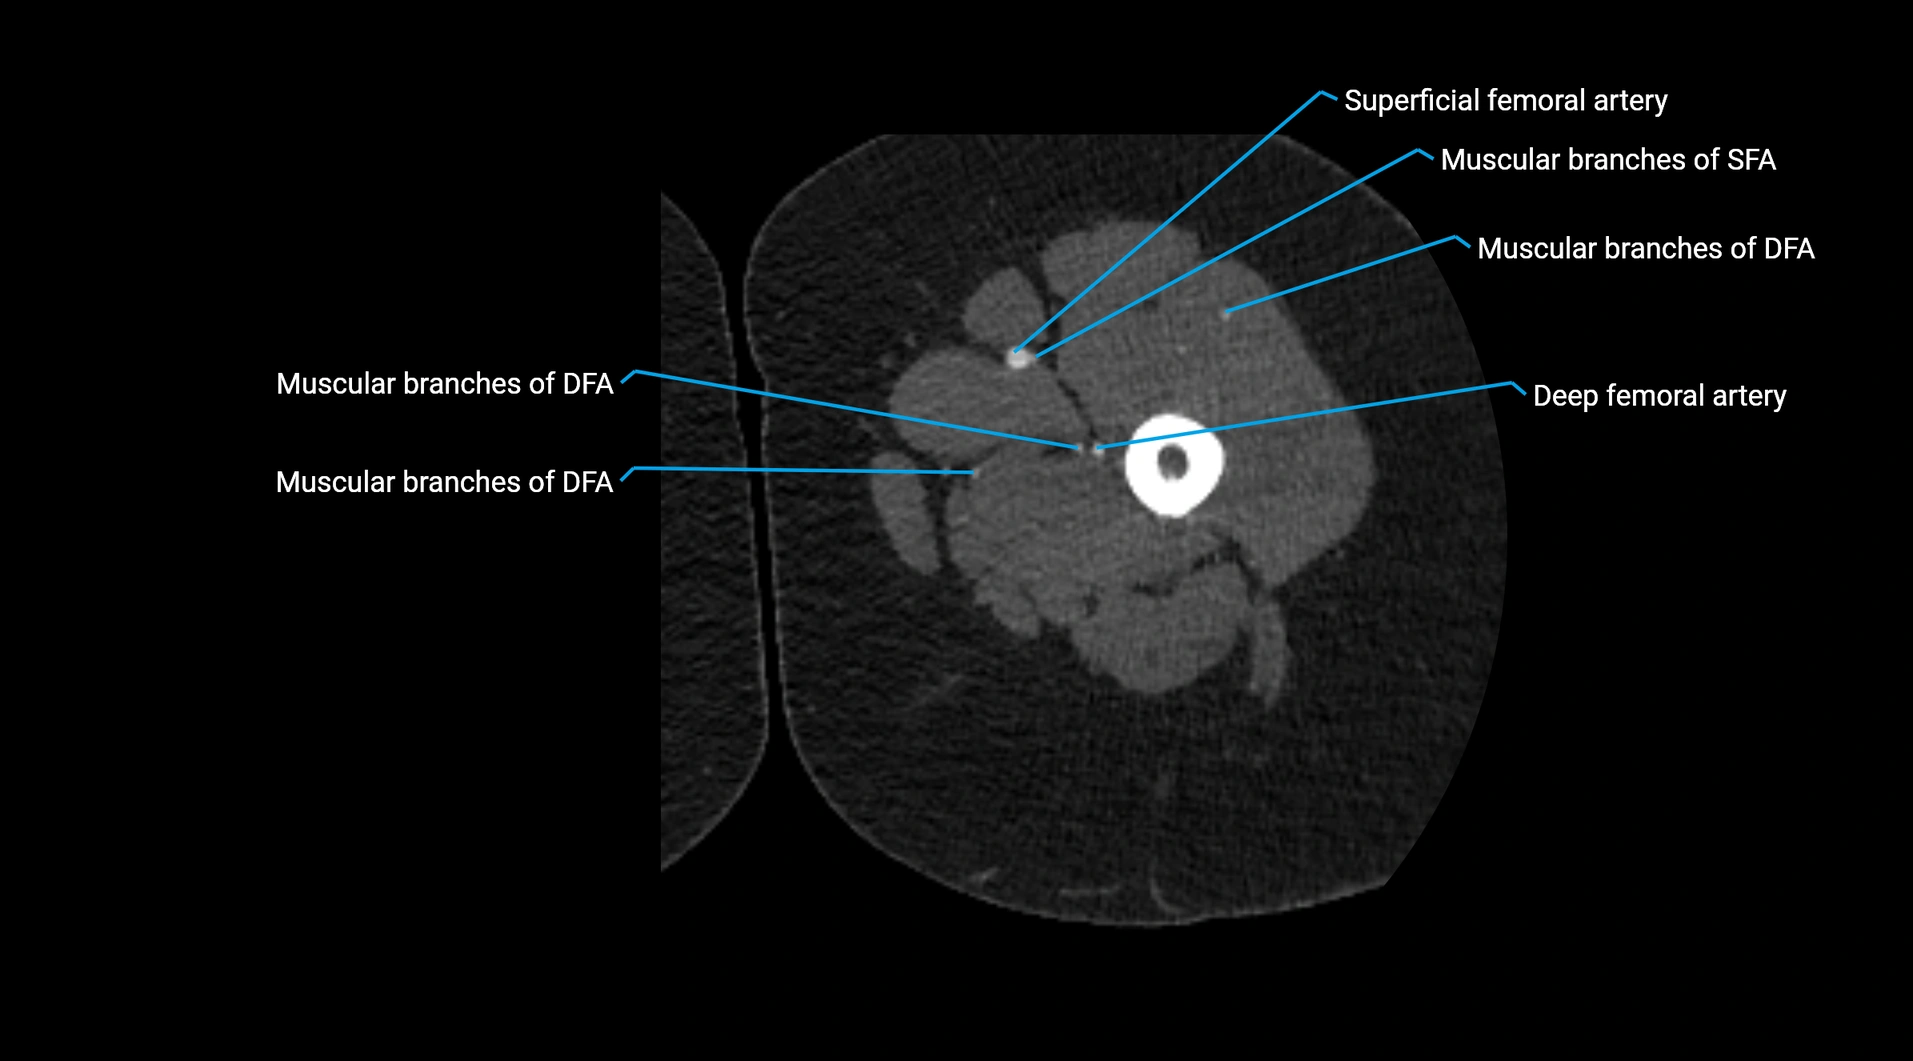

Contrast-enhanced CT (CTA):

• Gold standard for abdominal aortic imaging

• Provides excellent detail of lumen, wall, aneurysm, thrombus, and branch vessels

• Multiplanar and 3D reconstructions help in aneurysm measurement, stent graft planning, and dissection evaluation

• Detects acute rupture, traumatic injury, or occlusion with high sensitivity